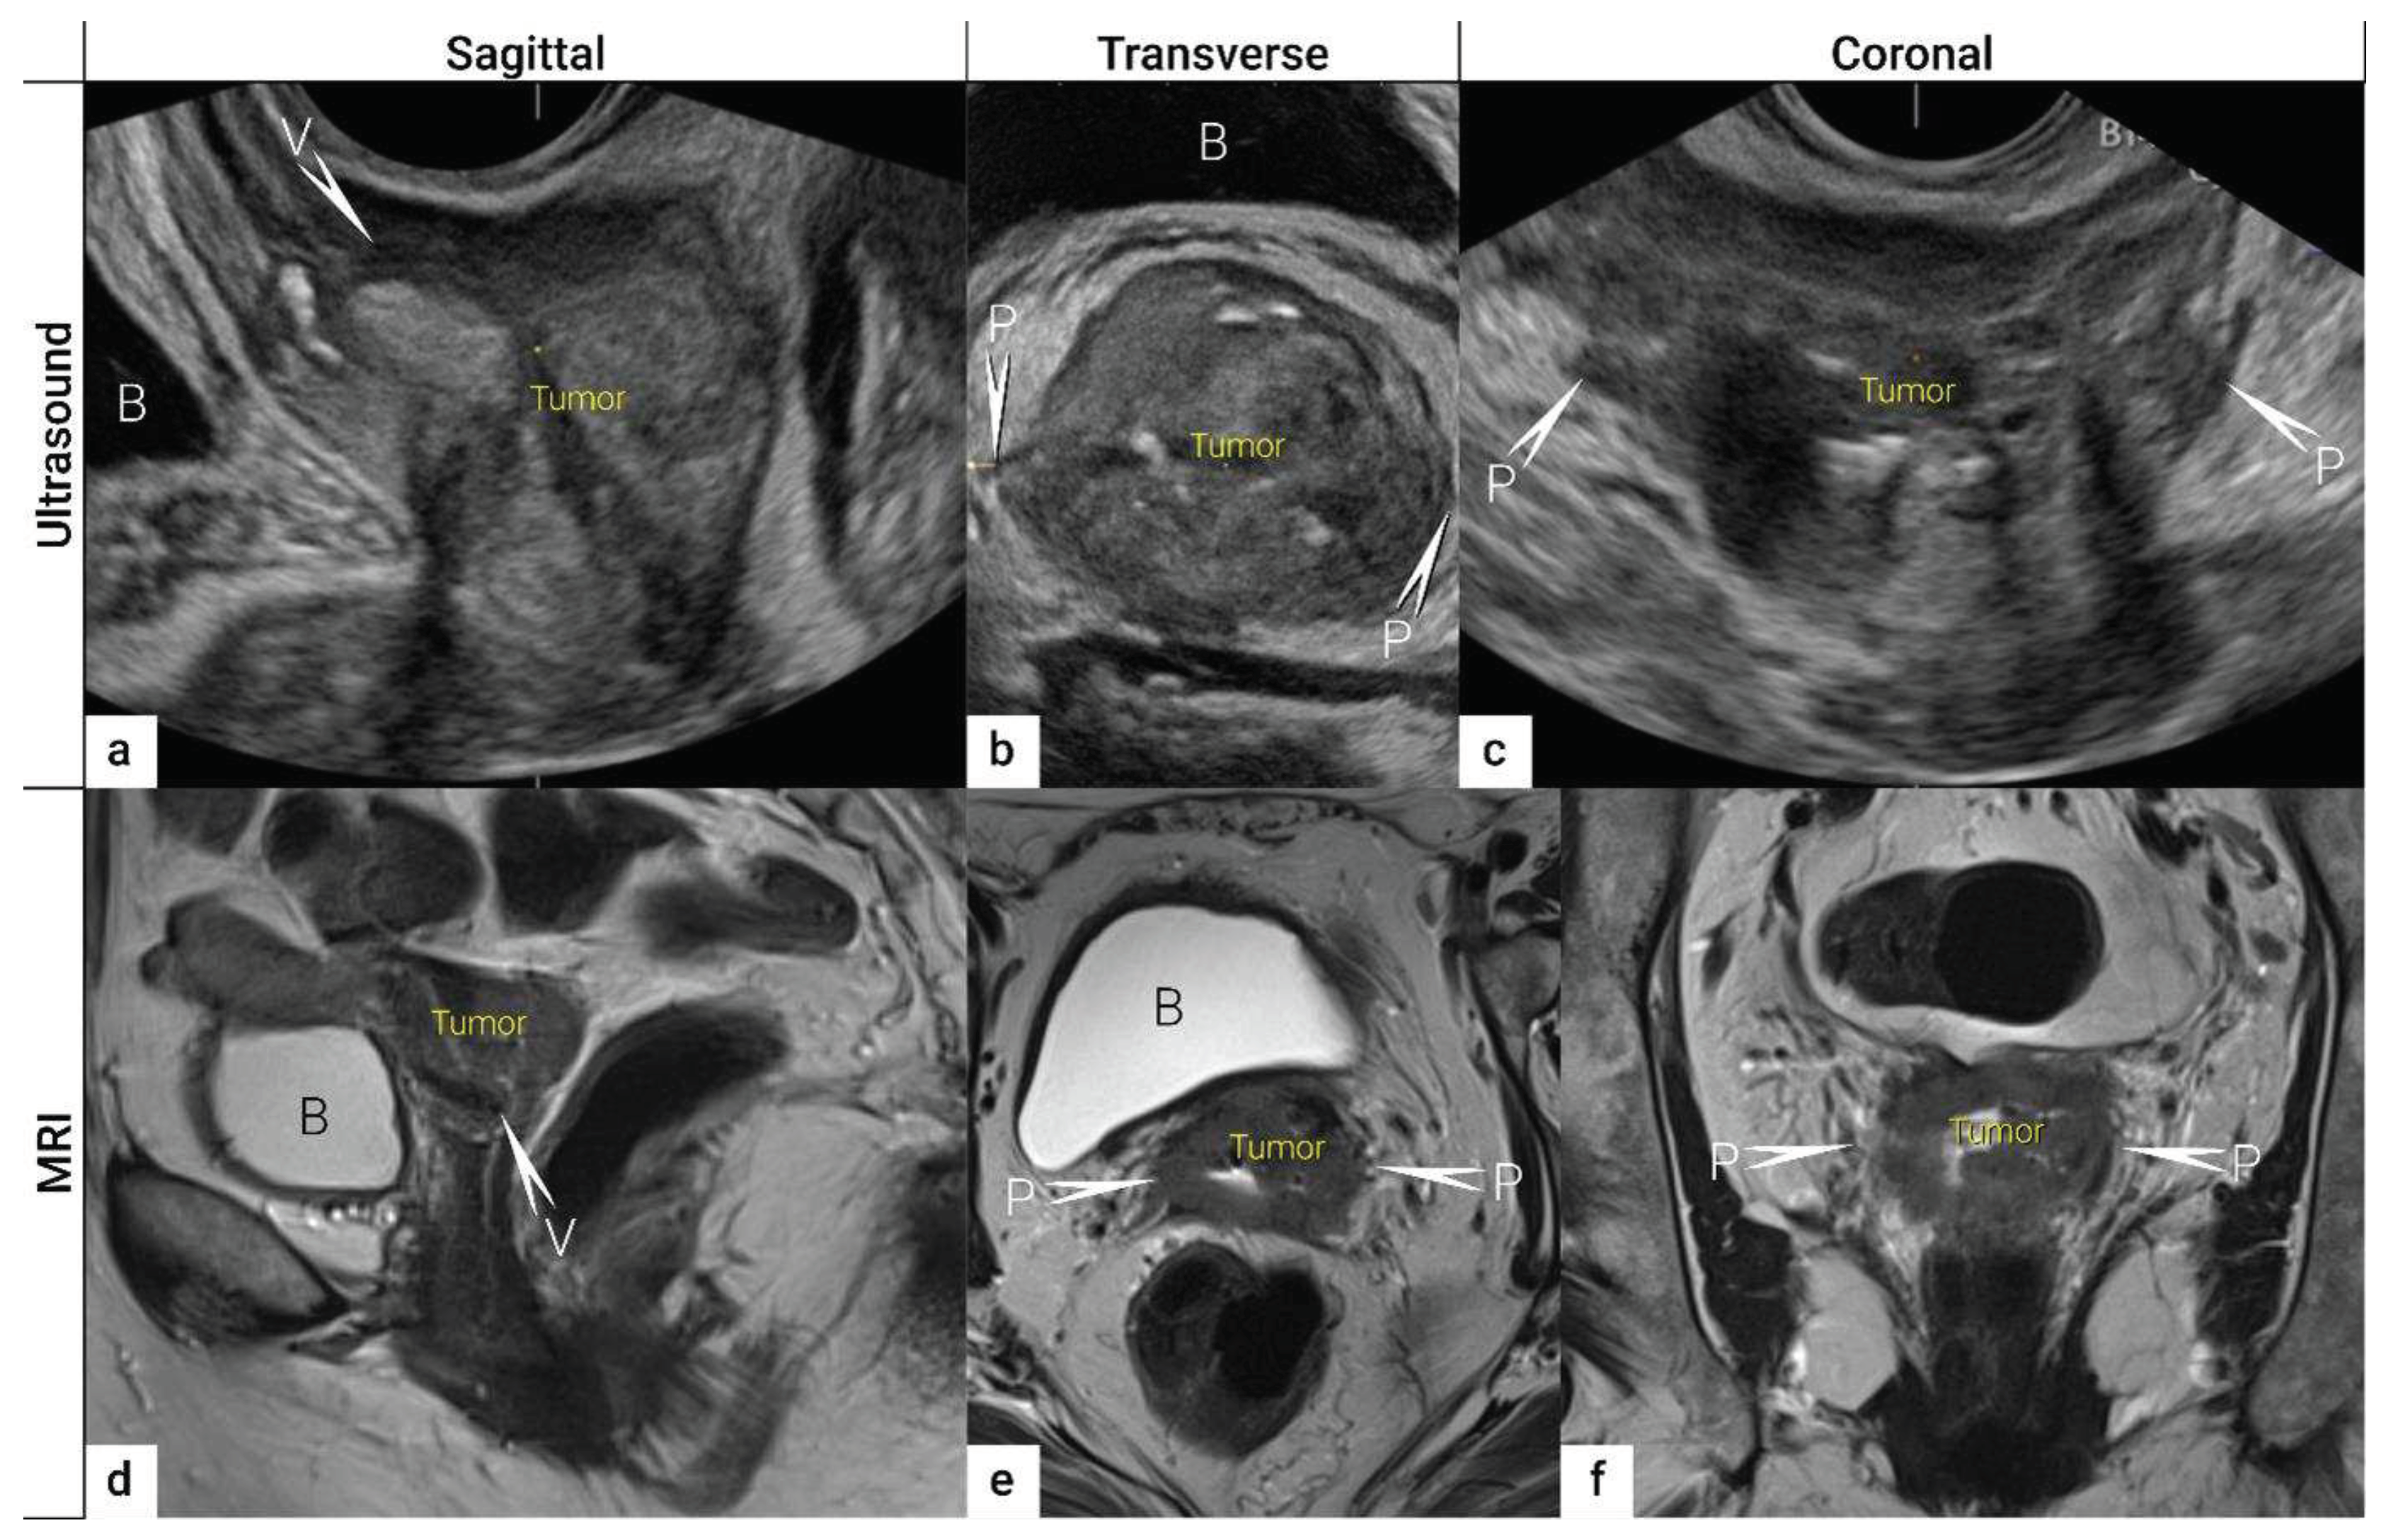

| IB | Carcinoma with deepest stromal invasion>5 mm, limited to the cervix uteri with size measured by maximum tumour diameter. | US: Highly vascularized hypoechogenic (squamous-cell carcinoma) or iso- / hyperechogenic lesion (adenocarcinoma) with intact hyperechogenic pericervical fascia and positive sliding sign between tumour and bladder/rectum. MRI: Tumour has intermediate to high signal on T2W images. Dynamic CE-T1W images depicts tumour as hyperintense in the arterial phase and iso- or hypointense in the venous phase. Tumours characteristically exhibit restricted diffusion on DWI (hyperintensity on high b-value images and low intensity on the ADC maps). Tumor does not disrupt the hypointense peripheral stromal ring (best seen on T2W images). |

| T2b | IIB | Parametrial tumour invasion but no pelvic side wall extension | US: Tumour infiltrates the hyperechogenic pericervical fascia, negative sliding sign, presence of hypoechogenic tumour projections into hyperechogenic parametria. MRI: Tumour disrupts the hypointense peripheral stroma and extends into the parametrium +/- abutting parametrial vessels on T2W images. |